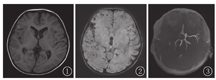

共23例,其中脑出血20例均为多发病灶,包括血肿和/或微出血。CT表现为片状高密度影,MRI常规序列因时间不同而不同,SWI呈低信号,且能显示微出血灶(图1、图2)。脑梗死2例中1例行CT检查,表现为右侧基底核区及额顶叶片状低密度影,其磁共振血管成像显示右侧大脑中动脉闭塞(图3),2例MRI平扫均呈T1WI低信号、T2WI等信号,DWI显示弥散受限。静脉窦栓塞1例,表现右侧乙状窦流空信号消失、T1WI高信号,增强检查见充盈缺损,呈"空Δ征"。

血管性病变是白血病常见的中枢神经系统并发症[2]。本组血管性病变约占46.9%(23/49例),以脑出血最多见,出血位置与血管分布区无关,与高血压所致脑出血不同。出血原因与高白细胞血症所致白细胞淤滞[3]、血小板减少、凝血功能异常、脓毒症等因素有关。Freireich等[4]对一组白细胞>300×109/L的高白细胞血症、白细胞危象、病程急性期死亡且伴有颅内出血的白血病患者进行镜检发现脑白质毛细血管内白细胞聚集、淤滞及白细胞结节形成,导致毛细血管壁破坏、出血,许多微出血灶融合形成肉眼可见的出血灶。本组20例脑出血中高白细胞血症(白细胞>100×109/L)达10例(50%),其中白细胞超过300×109/L者8例(40%),因此对于高白细胞血症患者应行影像检查排除脑出血风险。

左旋门冬酰胺酶是治疗成人和ALL的有效药物,几乎包含在所有ALL治疗方案中[5]。研究表明,该药物可导致血液中与凝血和纤溶有关的血浆蛋白缺失,与颅内出血、梗死、静脉窦栓塞等白血病脑血管并发症有关[6]。对于临床怀疑急性脑出血的患者,影像检查首选CT,但CT及常规MRI序列对微出血灶的检出敏感度均较低。而SWI序列是一种反应组织磁化属性的MRI新技术,可明显提高引起磁敏感效应物质的检出率。本组20例脑出血患者中17例MRI加扫SWI序列,其中8例患者SWI序列有新发现的微出血灶。因此对于白血病患者尤其高白细胞血症者评估出血风险时应行SWI序列检查。